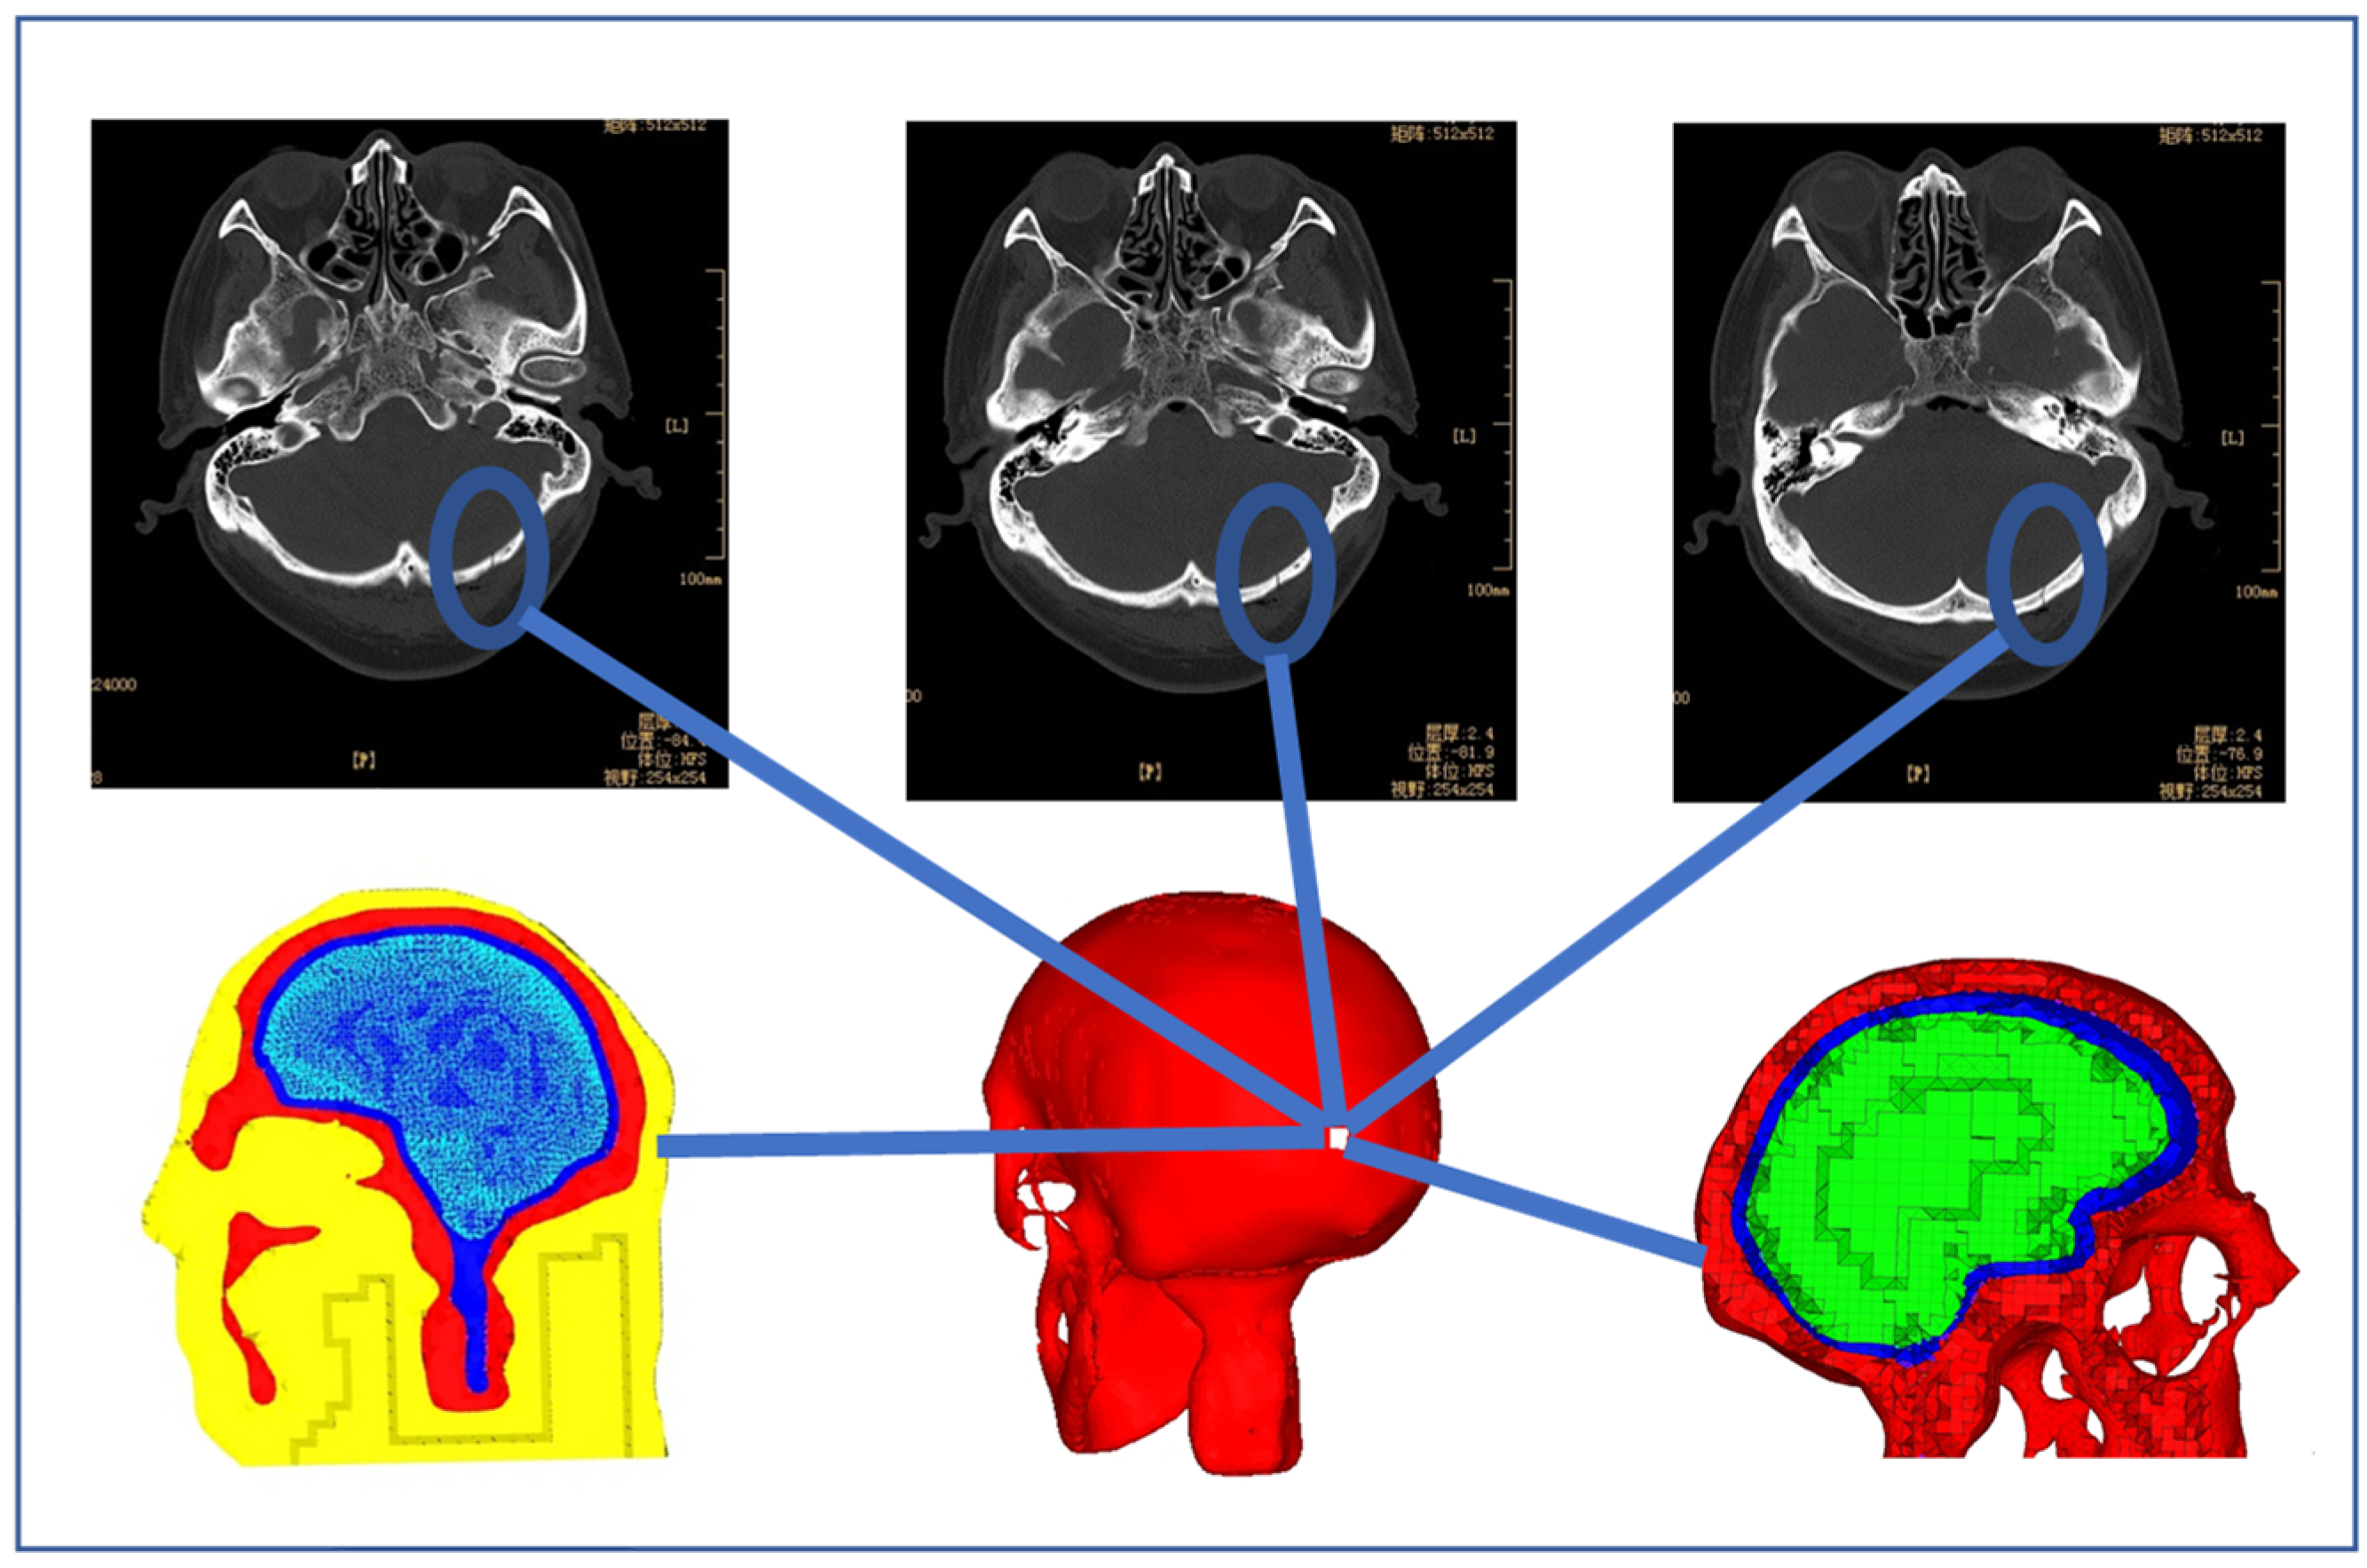

2.1. FE Human Head Model

| Component | Skull | Brain | Cerebrospinal Fluid | Scalp and Skin |

|---|---|---|---|---|

| No. of elements | 229,176 | 52,636 | 113,083 | 242,885 |